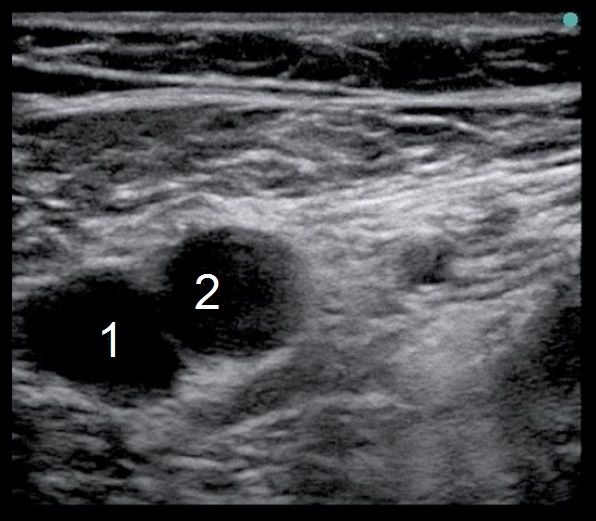

大腿神経ブロック - 大腿静脈・動脈特定の画像

大腿静脈

大腿動脈